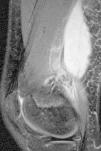

El primer caso fue un varón de 13 años previamente sano, que en el mes de agosto consultó por fiebre, dolor en la cadera izquierda irradiado a muslo y cojera de 7 días de evolución, refiriendo caída jugando al fútbol 4 días antes del inicio del cuadro. En la exploración física se objetivaron fiebre, flexión y rotación interna de la cadera izquierda con dolor a la movilización. Además existía dolor selectivo a la palpación del glúteo izquierdo, acompañado de inflamación y aumento de calor en la zona, objetivándose desplazamiento de la línea interglútea hacia la derecha. En la analítica sanguínea se apreció: velocidad de sedimentación globular (VSG) de 69mm/h y proteína C reactiva (PCR) de 13,70mg/dl. Las radiografías de cadera y fémur izquierdo fueron normales. Se realizó una ecografía abdominopélvica que describió una imagen hipoecogénica con refuerzo posterior adyacente al isquion izquierdo. La resonancia magnética nuclear (RMN) (fig. 1) evidenció una colección de 67×31mm con contenido líquido hiperintenso compatible con absceso del MOI y osteomielitis del coxal, con afectación del cartílago trirradiado. Se inició tratamiento con antibioterapia por vía intravenosa (cloxacilina y cefotaxima), requiriendo drenaje quirúrgico a la semana del ingreso por aumento del tamaño de la colección, con buena evolución posterior.